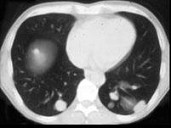

- 多项选择题女,38岁, 低热乏力并消瘦2月余,CT如图所示, 下列说法正确的是 ( )

A、左侧肾上腺区巨大的占位性病灶考虑为肾上腺癌

B、左侧肾上腺区巨大的占位性病灶考虑为嗜铬细胞瘤

C、左侧肾上腺区巨大的占位性病灶考虑为肾上腺腺瘤

D、肺内多发小结节病灶,考虑为肺转移癌

E、肺内多发小结节病灶,考虑为肺结核